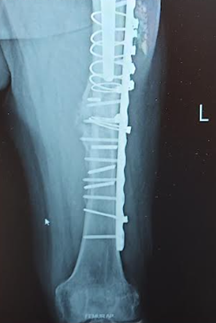

Second fixation, that's a lot of metal, including a few broken screws. Second photo shows healing callus